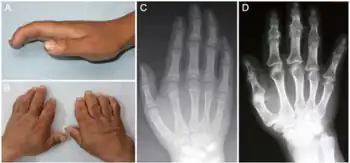

| a-d) Characteristics of child and adult Kashin-Beck disease individuals | |

Kashin–Beck disease (KBD) is a chronic, endemic type of osteochondropathy (disease of the bone) that is mainly distributed from northeastern to southwestern China, including 15 provinces.[1] Tibet currently has the highest incidence rate of KBD in China.[1] Southeast Siberia and North Korea are other affected areas.[1] KBD usually involves children ages 5–15. To date, more than a million individuals have suffered from KBD.[2] The symptoms of KBD include joint pain, morning stiffness in the joints, disturbances of flexion and extension in the elbows, enlarged inter-phalangeal joints, and limited motion in many joints of the body.[3] Death of cartilage cells in the growth plate and articular surface is the basic pathologic feature; this can result in growth retardation and secondary osteoarthrosis.[1] Histological diagnosis of KBD is particularly difficult; clinical and radiological examinations have proved to be the best means for identifying KBD.[4] Little is known about the early stages of KBD before the visible appearance of the disease becomes evident in the destruction of the joints.[4]

The clinical presentation of this condition is as follows:[7]

- Restricted movement

- Pain in joints

- Large joints

- Varus deformity of hip

- Thick fingers